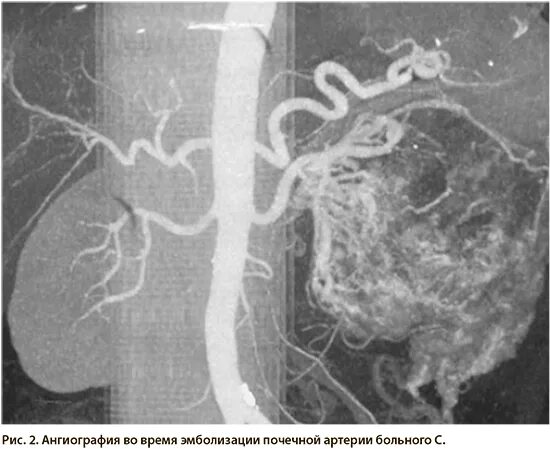

Эмболизация гемангиомы